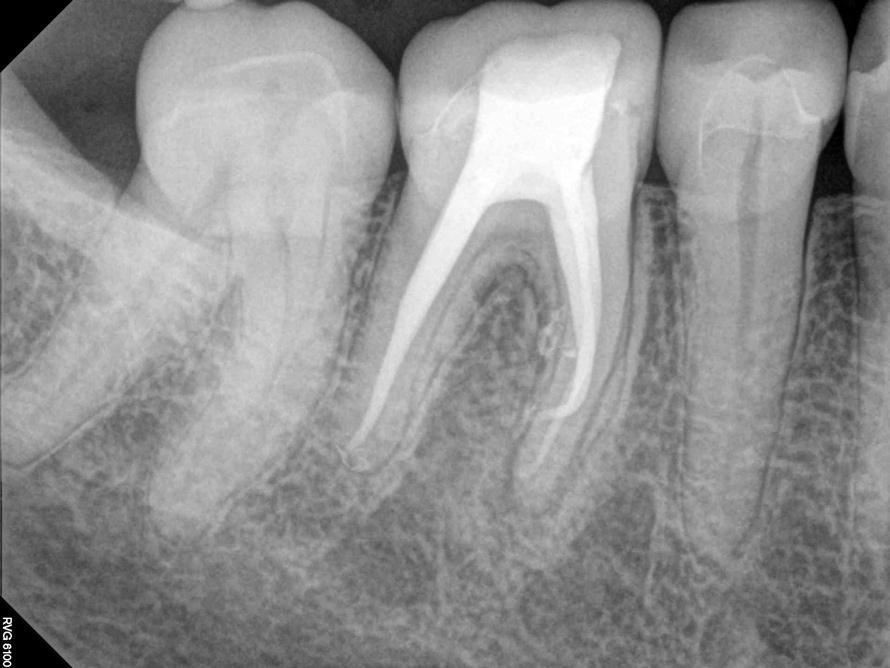

Fig 7. Cases treated by the continuous wave of condensation technique using gutta percha and epoxy resin sealer.

Figure 7

Fig 8. Cases treated by the continuous wave of condensation technique using gutta percha and epoxy resin sealer.

Figure 8

A version of warm vertical compaction, termed the continuous wave of condensation, is one of the most widely utilized obturation techniques19 (Figure 7 and Figure 8). This method involves placement of a single, tapered gutta percha cone fit to the same size as the master apical file with sealer, and downpacked with a controlled electric heat source. Based on the rotary instrumentation system used, either 04 or 06 tapered, ISO standardized apical size gutta percha cones corresponding to the final size and shape of the prepared canal can be placed with an appropriate sealer. A plugger heated to 200°F is introduced into the apical third of the root as determined by the working length to condense the apical portion of gutta percha. The heating element is turned off but left in place for an additional 5 seconds to allow slight cooling before a quick burst of heat. The heating element is removed with the coronal portion of excess gutta percha. Following this, the remainder of the canal space is filled using flowable gutta percha delivered via a motorized backfill device to the level of the chamber floor. This method can be hybridized with lateral compaction, in which spreaders are used to add accessory cones, when the shape of the canal does not allow for a tight fit of the ISO sizes of gutta percha points.